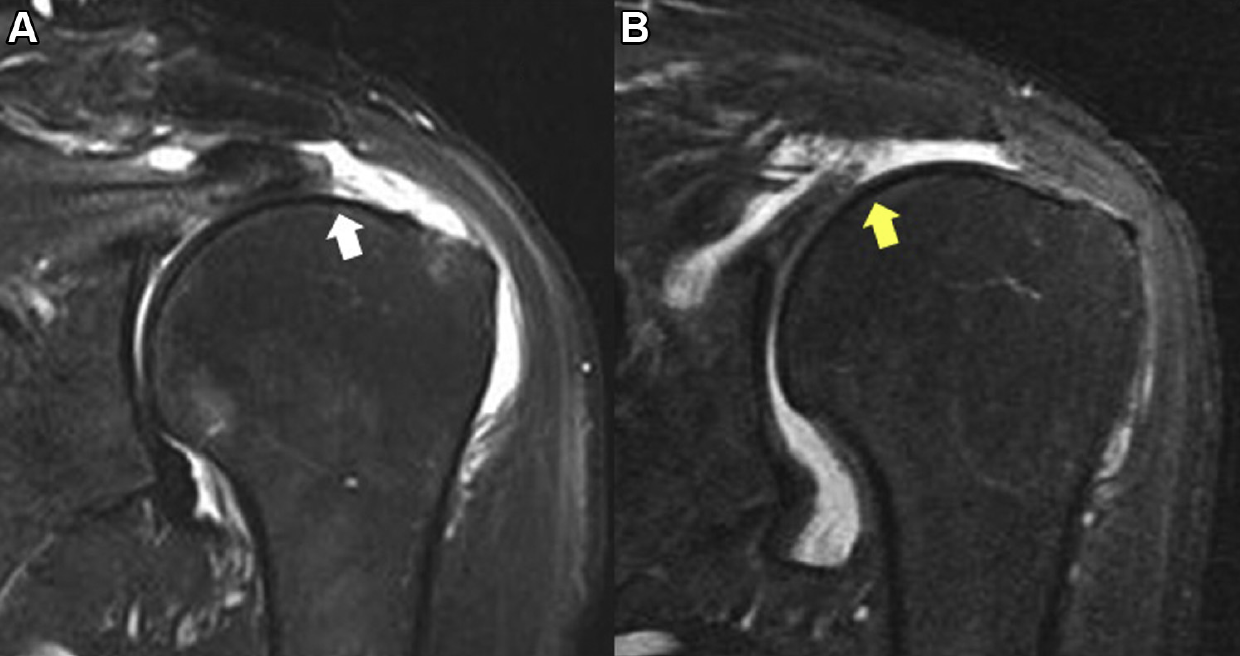

Shoulder Arthritis/Joint Replacement Rotator cuff tears What does a Shoulder Pain Arthritis Or Rotator Cuff The most important facts about cuff tear arthropathy (shoulder arthritis with a. Rotator cuff tear arthropathy is a type of shoulder arthritis that can develop after a massive and prolonged rotator cuff tear. If you experience shoulder pain at night that makes it difficult to fall asleep or jolts you awake, you may have a tear in one or more. Shoulder Pain Arthritis Or Rotator Cuff.